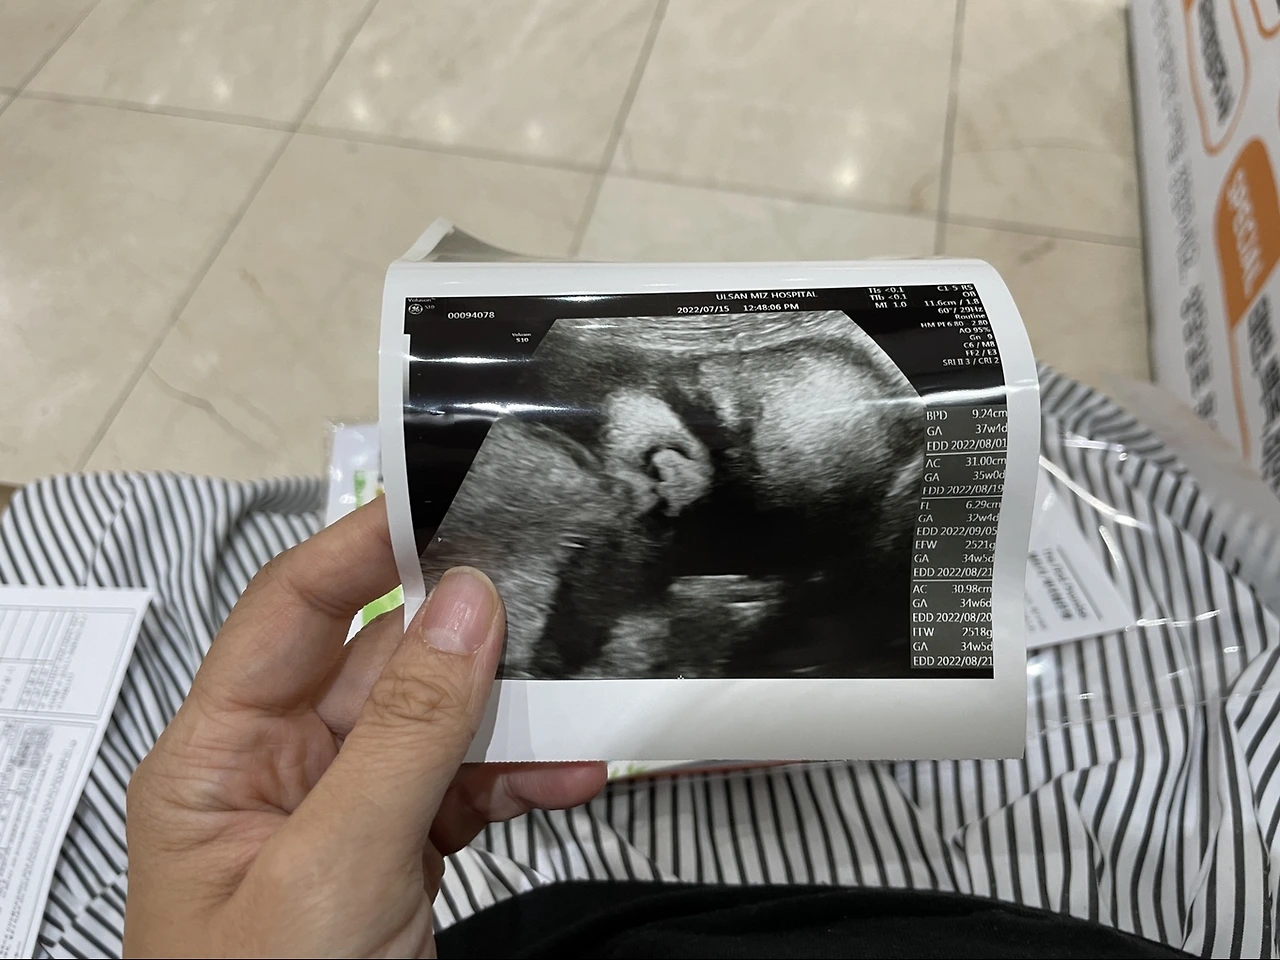

임신 37주 4일 자 수술 날짜까지 잡고 왔다.

남은 출산 4일 전, 제왕절개는 날짜를 정할 수 있지만 긴급 진통이 오면 그 길로 수술하러 가야 한다.